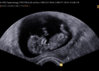

- På vei: 12+3

- Måned: 3 svangerskapsmåned

- Trimester: 1. trimester

- Ultralyd: Ordinær UL 2 September